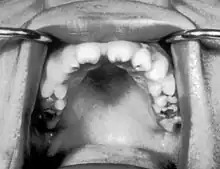

| Notched incisors in congenital syphilis | |

Hutchinson's teeth are small teeth with notches on their biting surfaces, seen in congenital syphilis.[1]

Notched incisors known as Hutchinson's teeth which are characteristic of congenital syphilis